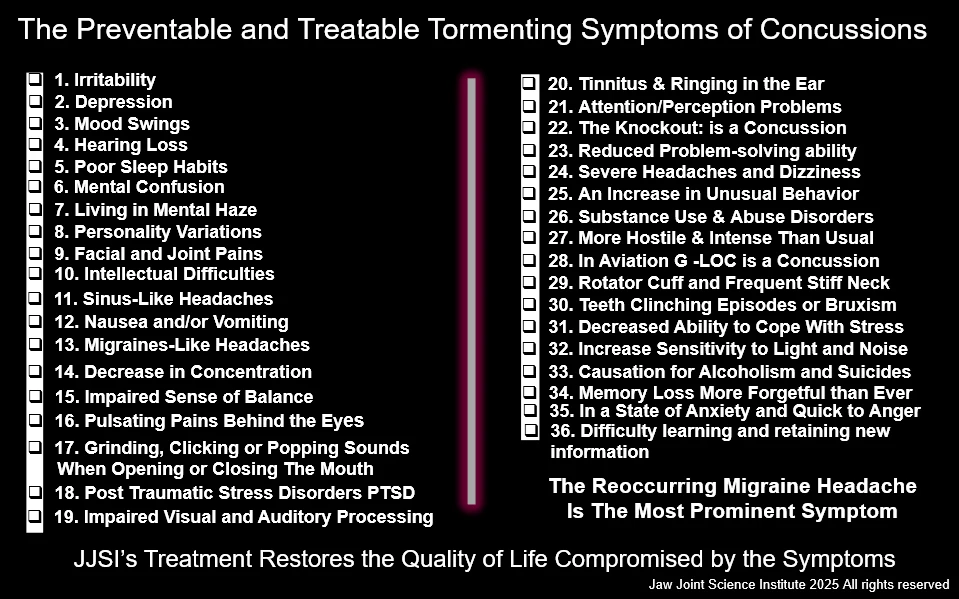

Some of the treatable symptoms of TMJ fractures associated with concussions include:

Recurring Headaches

Irritability

Depression

Mood Swings

Hearing Loss

Mental Confusion

Nausea/Vomiting

Impaired Sense of Balance

Tinnitus